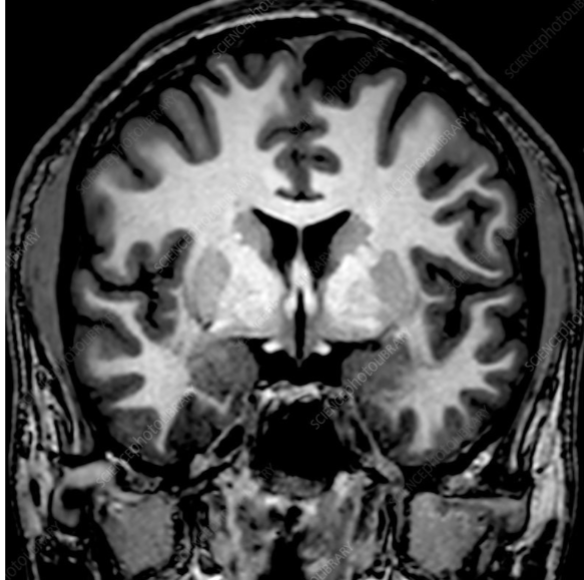

Horizontal/axial cut

knowt flashcard image

2

New cards

coronal cut